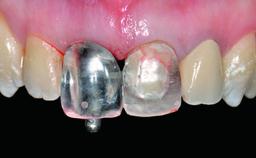

Replacement of a Compromised Upper Right Central Incisor: Hard- and Soft-tissue Augmentation, Late Placement of an RC Bone Level Implant

Abutment Type CAD/CAM

Prosthesis Type FDP

Loading Protocol Conventional or early

Retention Screw-retained Screw-retained